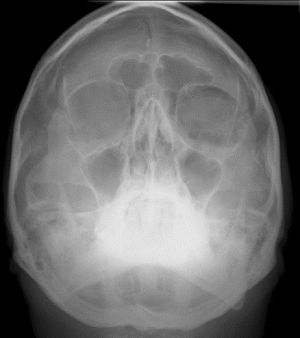

Plain radiographs: X-rays may reveal air within the orbital cavity. This modality has a high false negative rate of 50% and may not detect small amounts of air or subtle fractures.[9] Additionally, vertical globe dystopia is a physical exam finding, which can look like a crescent-shaped area of radiolucency in the superior aspect of the orbit on a radiograph (see Figure 1). This finding is also termed the “black eyebrow sign”[6][10][11].